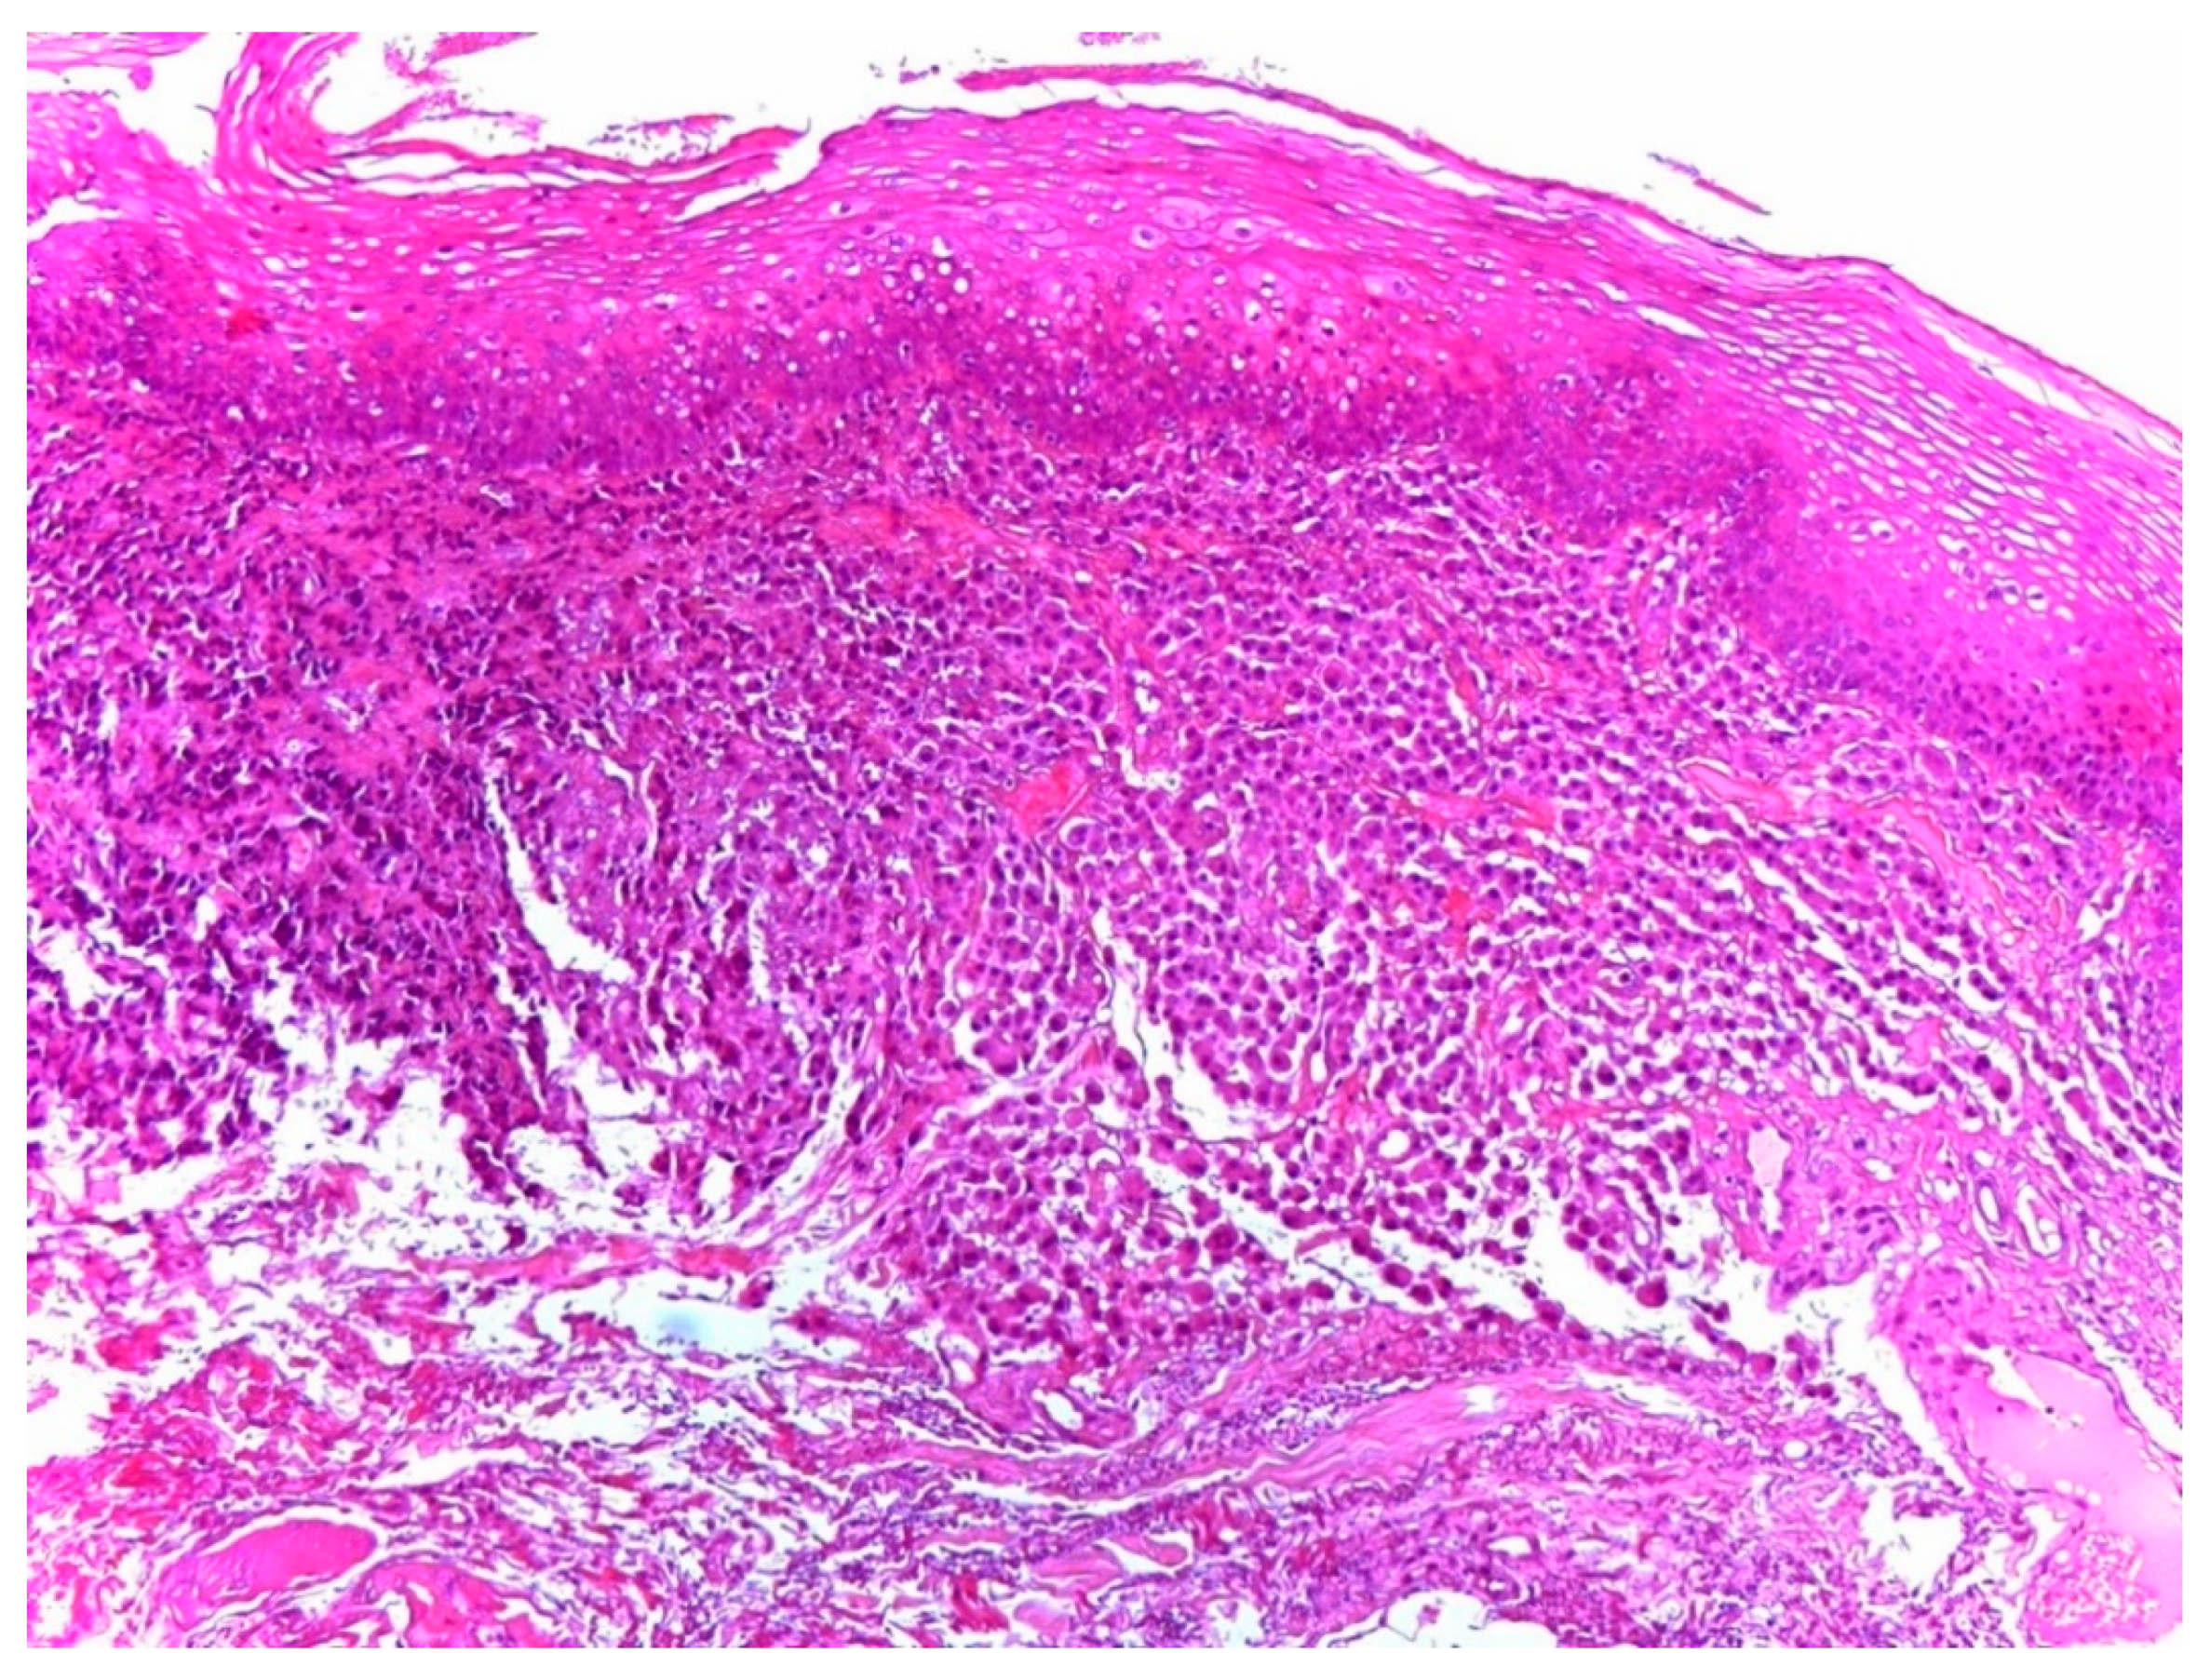

2. Case Report

3. Discussion